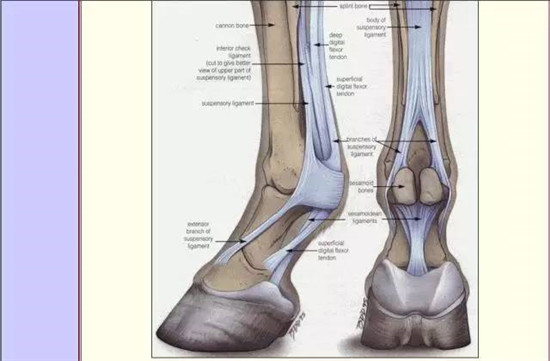

2.找到球节和冠关节

▲示意图(前肢)

籽骨是支持装置的一部分。悬韧带在球节部位走向分成两侧支,分别在两端近端籽骨侧面牵引。在马匹快速运动的过程中,球关节重复性过度伸展或者受外力作用,籽骨可发生疲劳性损伤或者外力损伤。常发于运动马匹,前肢多发。

▲近端籽骨和悬韧带